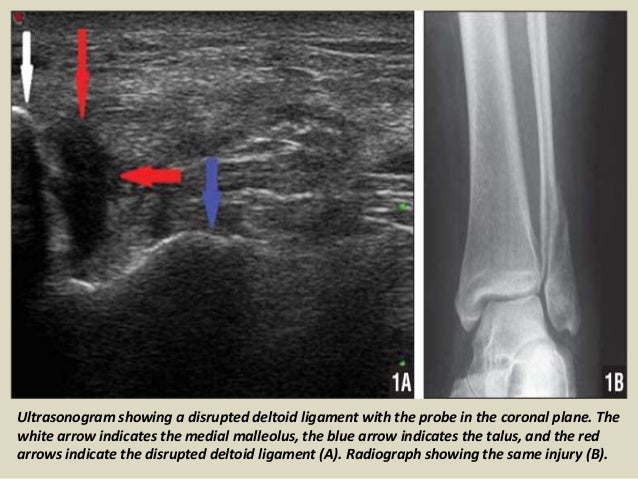

Ultrasonogram showing a disrupted deltoid ligament with the probe in the coronal plane. The

white arrow indicates the medi...

75. 75. MEDIAL COMPARTMENT Because of the low incidence of eversion ankle sprains and the thickness of the deltoid ligament is rarely injured in isolation and when the injury does not usually full thickness. Usually accompanied by lesions of the medial malleolus and lateral displacement of the talus, with consequent widening of the ankle mortise. Ultrasound is useful for differentiating ligament injury of the posterior tibial tendon injury (TP) adjacent, they have similar symptoms. The inability to visualize the deltoid ligament may indicate tear , but this is not considered a reliable sign as its full ultrasound is not always possible.

78. 78. Ultrasonogram showing a disrupted deltoid ligament with the probe in the coronal plane. The white arrow indicates the medial malleolus, the blue arrow indicates the talus, and the red arrows indicate the disrupted deltoid ligament (A). Radiograph showing the same injury (B).